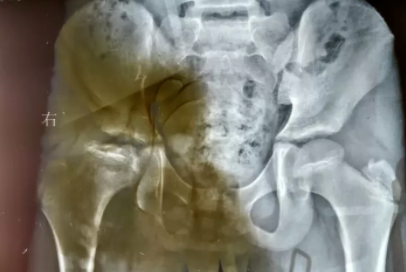

- 编号

FS16040026 姓名:刘奶奶 性别:女 年龄:74岁

- 病情

风湿性关节炎晚期 病史:40年+

- 治疗

治疗后患者左膝关节肿胀现象已消除。膝关节屈伸度有所增加,下蹲情况改善。患者自述双腕关节疼痛减轻,肿胀消除。